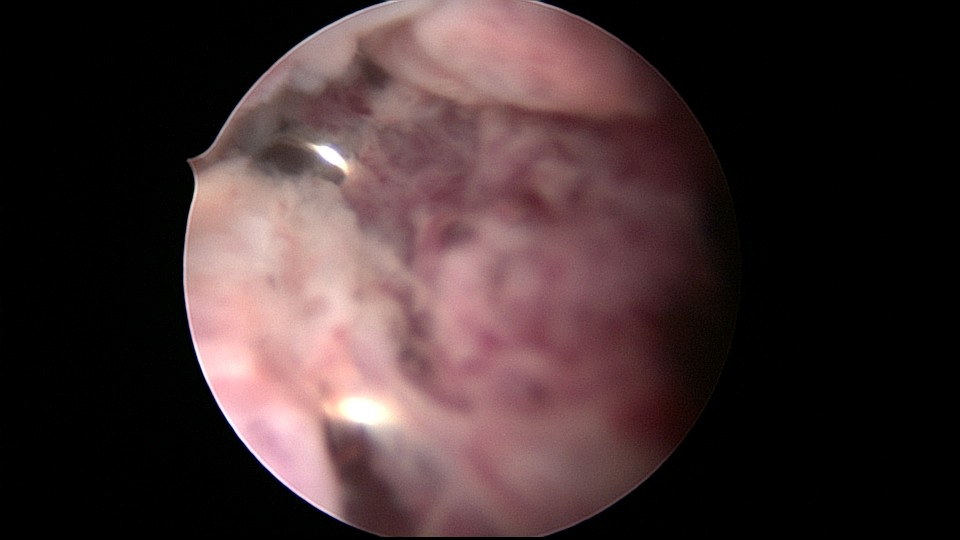

患者45岁,G1P2,剖宫产双胎1次(自然妊娠)。安环23年,异常子宫出血月经淋漓不尽2个月,外院取环残留,环断裂,外院医生述取出约10cm变形环段,腹部平片见O型环断裂,断端指向宫颈管。宫颈位于前穹隆顶端,暴露困难,艰难置入宫腔镜,见内膜杂乱,反复寻找才发现O型环残环,残环两侧与宫壁嵌顿,异物钳抓取数次均滑脱,顺宫颈管向下寻找,在宫颈管中上段找到环断端,异物钳缓慢拉出断端至宫颈外口,中弯钳配合卵圆钳牵拉,环断裂,取出约10cm环残段。宫腔镜再次进入宫腔,找到剩余残环,异物钳夹取,多次滑脱,取环钩顺着镜鞘外侧进入宫腔,钩住残环,缓慢下拉至宫颈外口,中弯钳配合卵圆钳拉出约12cm环残段,宫腔镜再次探查宫腔,镜下未见环残留,取内膜送病检。术后病人离院时复查B超,有强回声带,因宫腔少许气体干扰,无法确定是否环残留,嘱病人一周后复查B超,确定无环残留。第一次遇到这么脆弱的金属圆环,很容易断裂。病检为子宫内膜增生,不伴非典型增生。